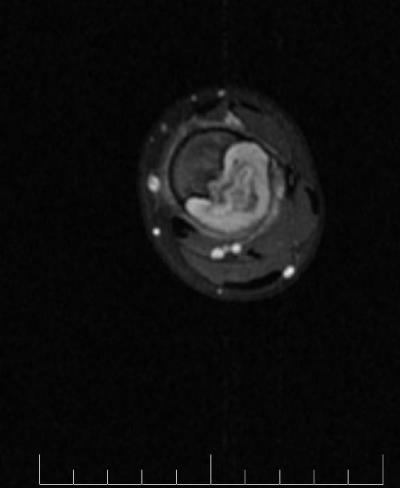

MRI demonstrates low signal intensity on T1 weighted images (Figure 2, Figure 11 and Figure 12). T2 weighted images demonstrate high signal intensity (Figure 3, Figure 13). Post gadolinium contrast T1 weighted sagittal view demonstrates diffuse heterogenous enhancement (Figure 14). Post gadolinium contrast T1 weighted axial view demonstrates peripheral nodular enhancement (Figure 15).

Figure 13: MRI axial T2 of the left tibia.

Figure 14: MRI sagittal T1 fat sat post gadolinium of the left tibia.